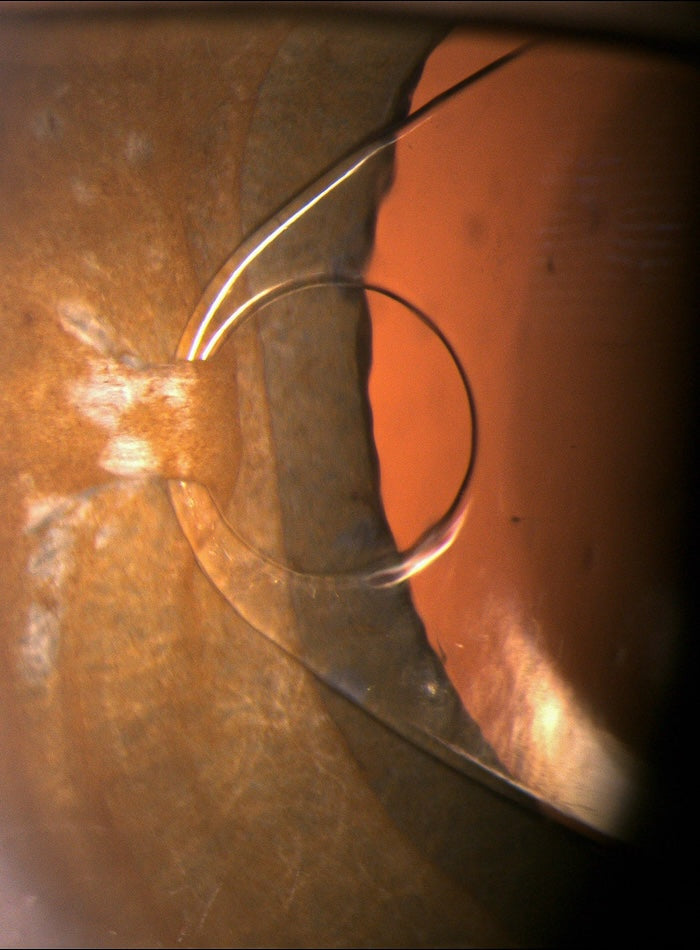

Iris-claw uchytenie afakickej IOL

Detail uchytenia afakickej vnútroočnej šošovky s haptikou typu Iris-Claw priamo na dúhovku.